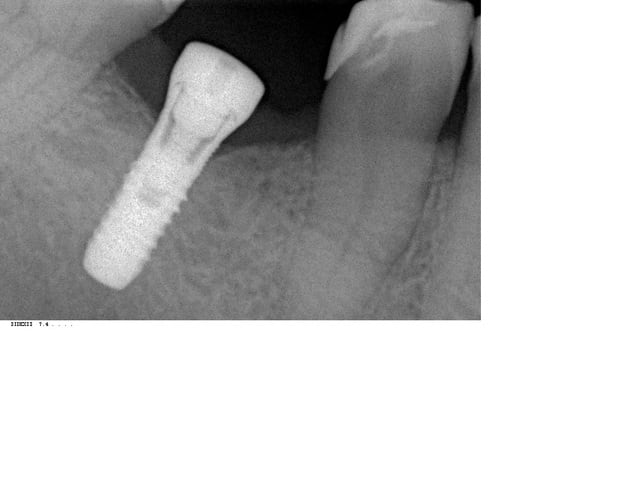

-un homme de 53 ans ,bonne hygiène ,2cigarettes par jour,36et46 extraites depuis 15 ans ,il y a 4 mois mise en place de 2 Aesthetica+.

pas de problèmes particuliers lors de la pose sauf que je prévoyait du D2 mais c'etait du D1 jai mis les 2 vis de cicatrisation,les suites operatoires etaientt normales avec une belle gencive attachée pas d'inflammation.surprise 4 mois plus tard cratérisation sur 36 et lyse angulaire. cliniquement pas de spires exposées,pas de mobilité,prévoir une accélération du phénomène apres mis en charge?merci de votre aide.

Je connais bien cet implant. A mon humble avis, il a été posé en force, peut etre parce que le foret terminal était de trop petit diamètre (os D1 alors qu'on attendait du D2) . Cet implant tolère mal l'insertion forcée car il est cylindrique , surtout à la mandibule. La force étant excessive , le col a subi une compression excessive, ce qui a créé une ischémie de l'os crestal et donc une cratérisation à court terme.

ça me fait plus penser à un sous-forage (ou manque de sur-forage) au niveau cortical qu'à un problème de connectique.

Pas un problème d'échauffement, mais plutôt de forces excessives générées sur un os insuffisamment capable de les absorber.

Salut,l'implant était légèrement supracrestal(une spire) l'edentement avait 15 ans voici le scan.